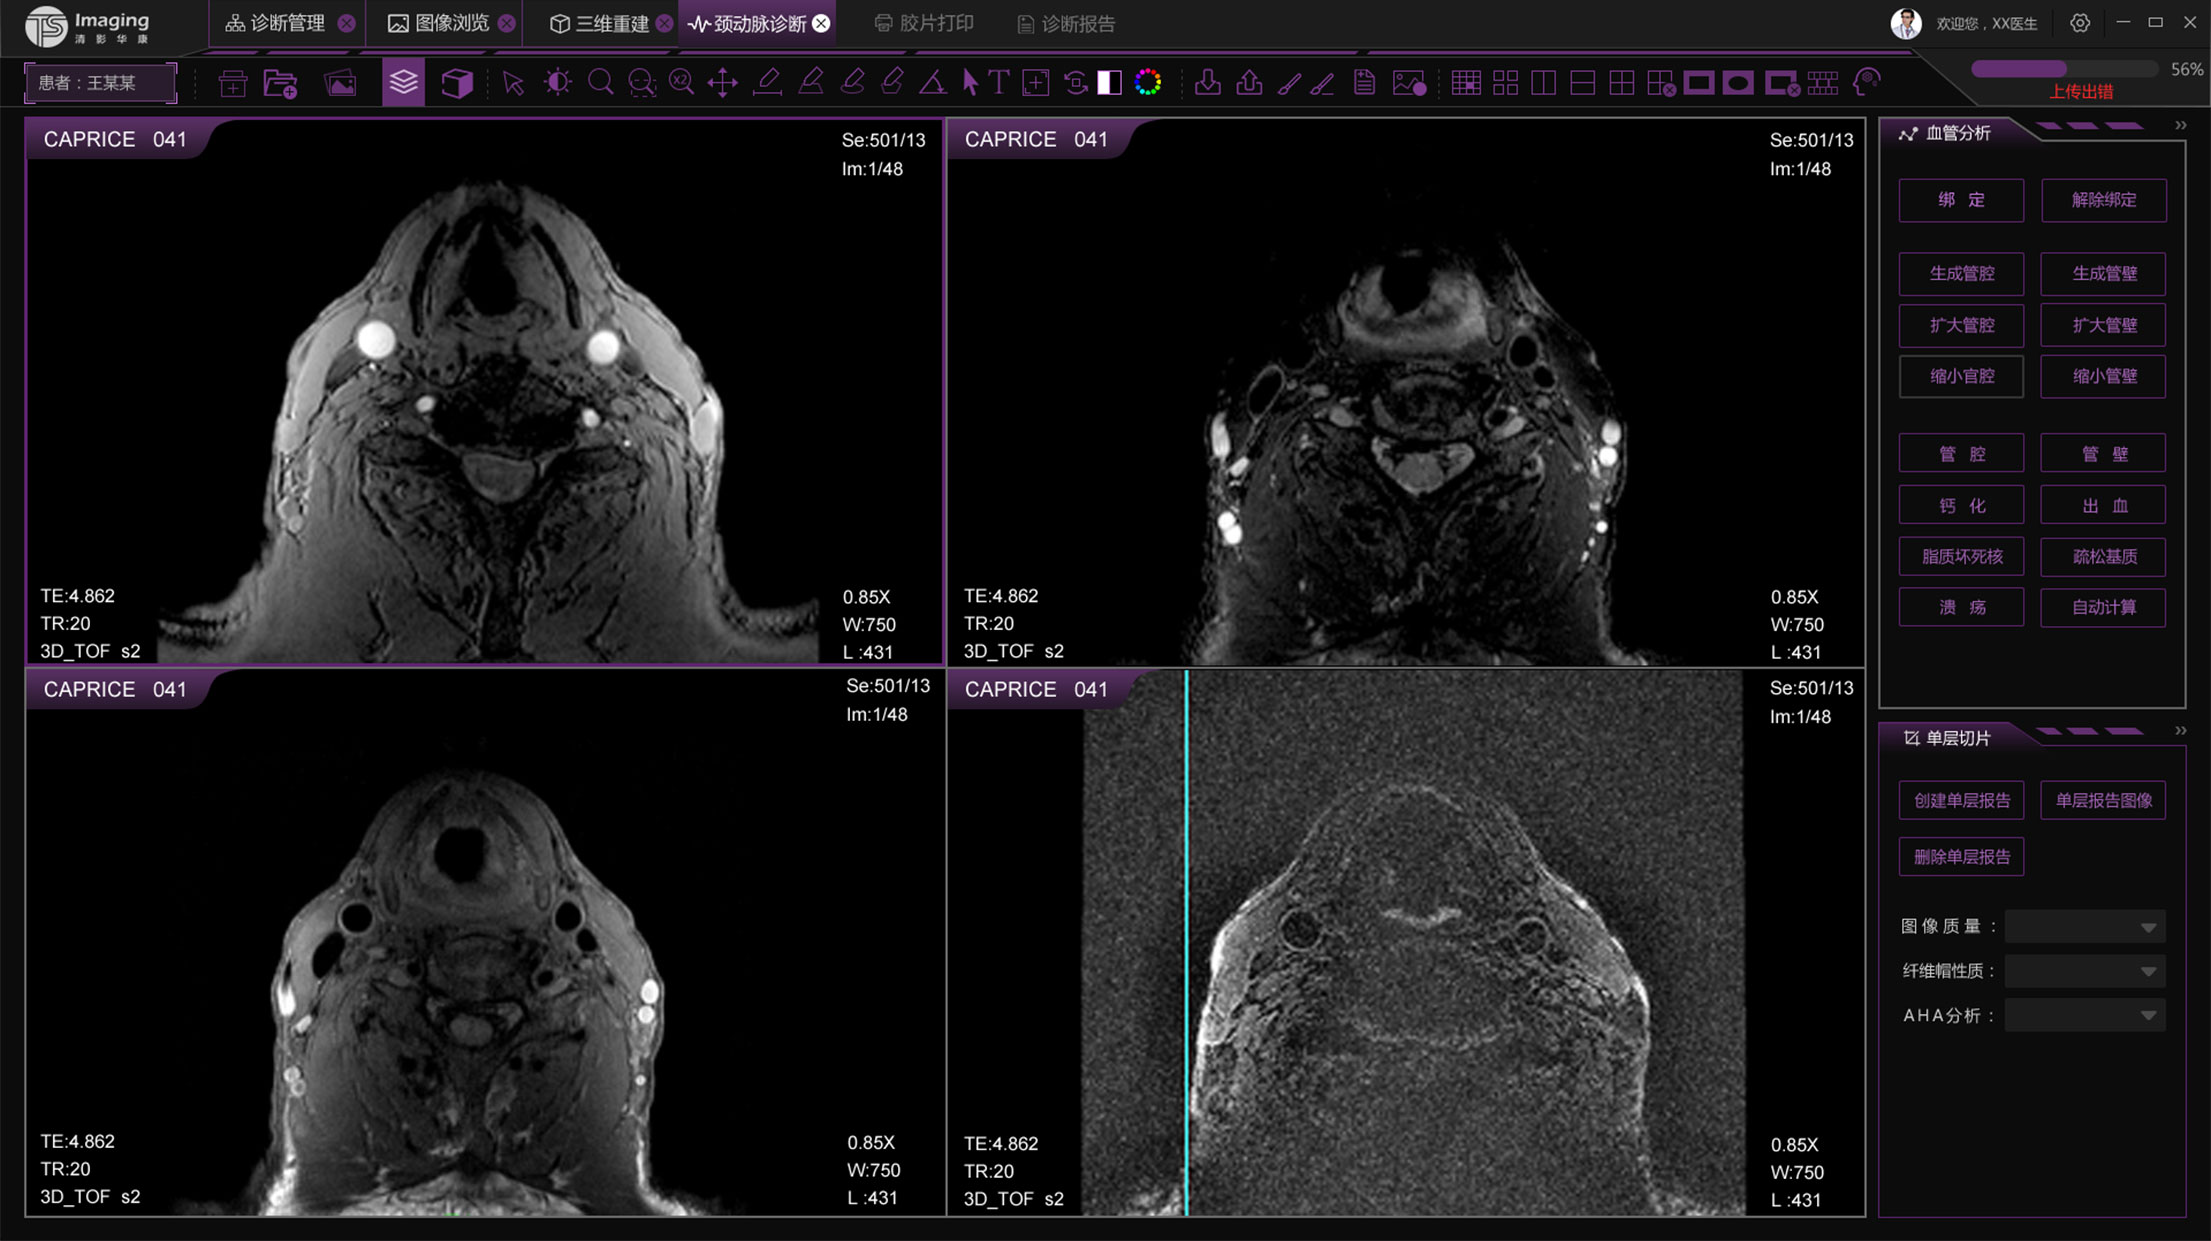

頸動脈診斷頁面

頸動脈診斷頁面整體布局和三維重建比較相似,最大的區(qū)別是右側(cè)的操作區(qū)域,血管分析都為按鍵操作,通過間隔的大小分成三部分。單層切片除了按鍵還有下拉菜單的操作。